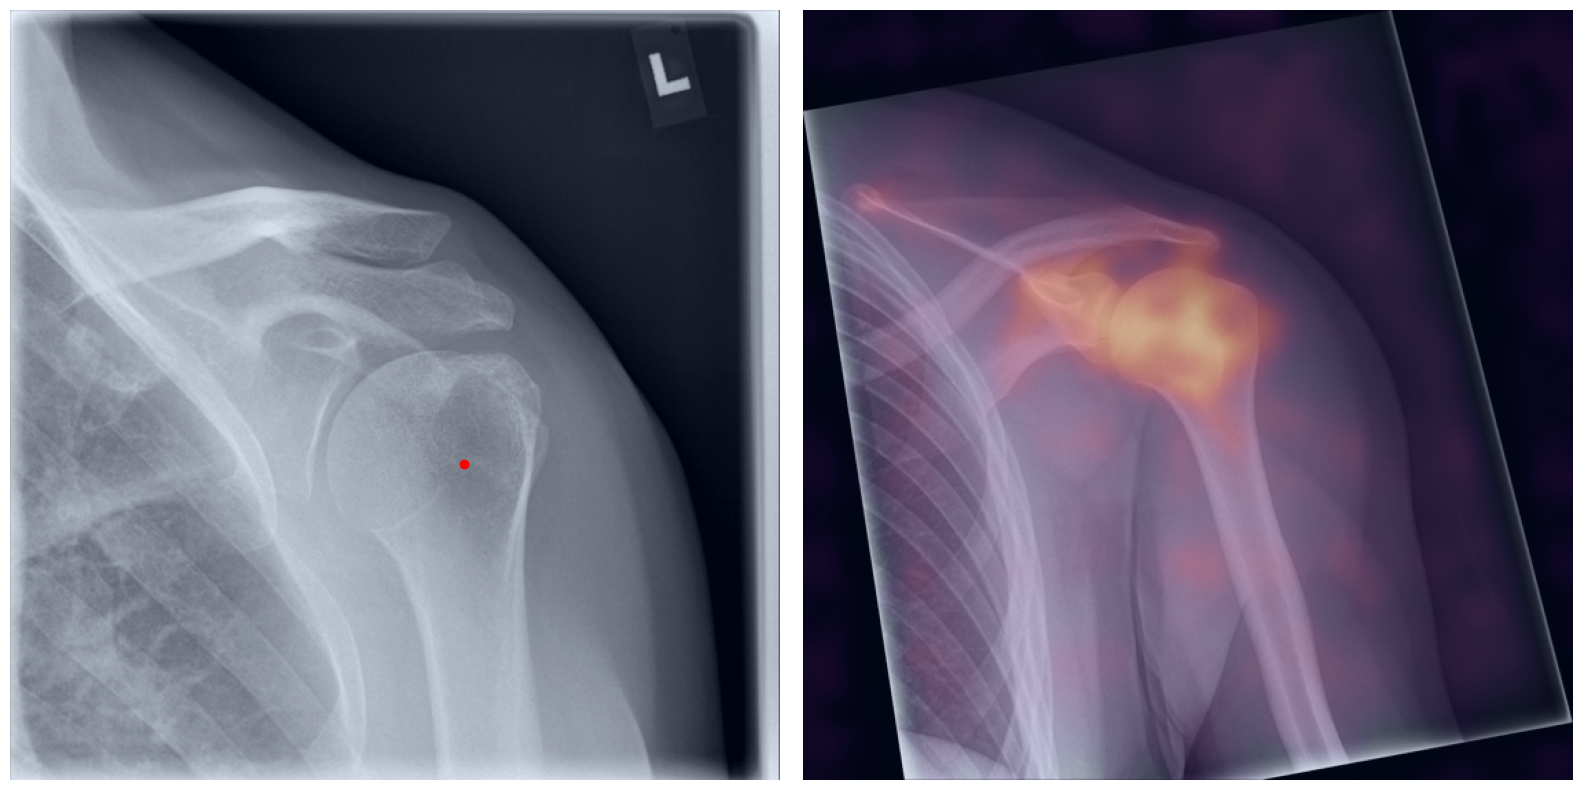

Behind the Curtain: Visualizing the Inner Workings

The process of establishing a dense match between two images relies on abstract feature representations for each position in both the reference and target images. To better understand which information is encoded by the AI, we examined the feature similarities between a specific position within the reference image and the entire target image. Our findings show that the AI captures both semantic and texture features. The matching process utilizes this encoded information, along with precise positional data, to create a reliable mapping between the images.

Hover your mouse over the image to stop automatic transitions.